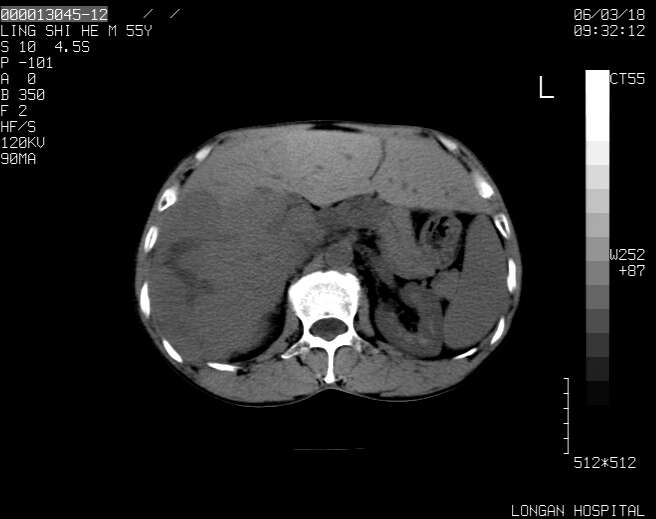

以下是引用guzhongliangddd在2006-3-21 22:13:00的发言:[br]病灶主要位于肝右叶的后份,内见异常血管,门脉主干及右支受侵{提示有癌栓形成},门腔间隙内见增大淋巴结。肝左叶内未见异常。

以下是引用zhuxinli在2006-3-22 1:23:00的发言:[br][br] 病灶主要位于肝右叶的后份,内见异常血管 .门脉右支截断,右叶前段早期强化(考虑动静脉漏),腹膜后肿大淋巴结,病灶逐渐强化,考虑为胆管细胞癌[br]